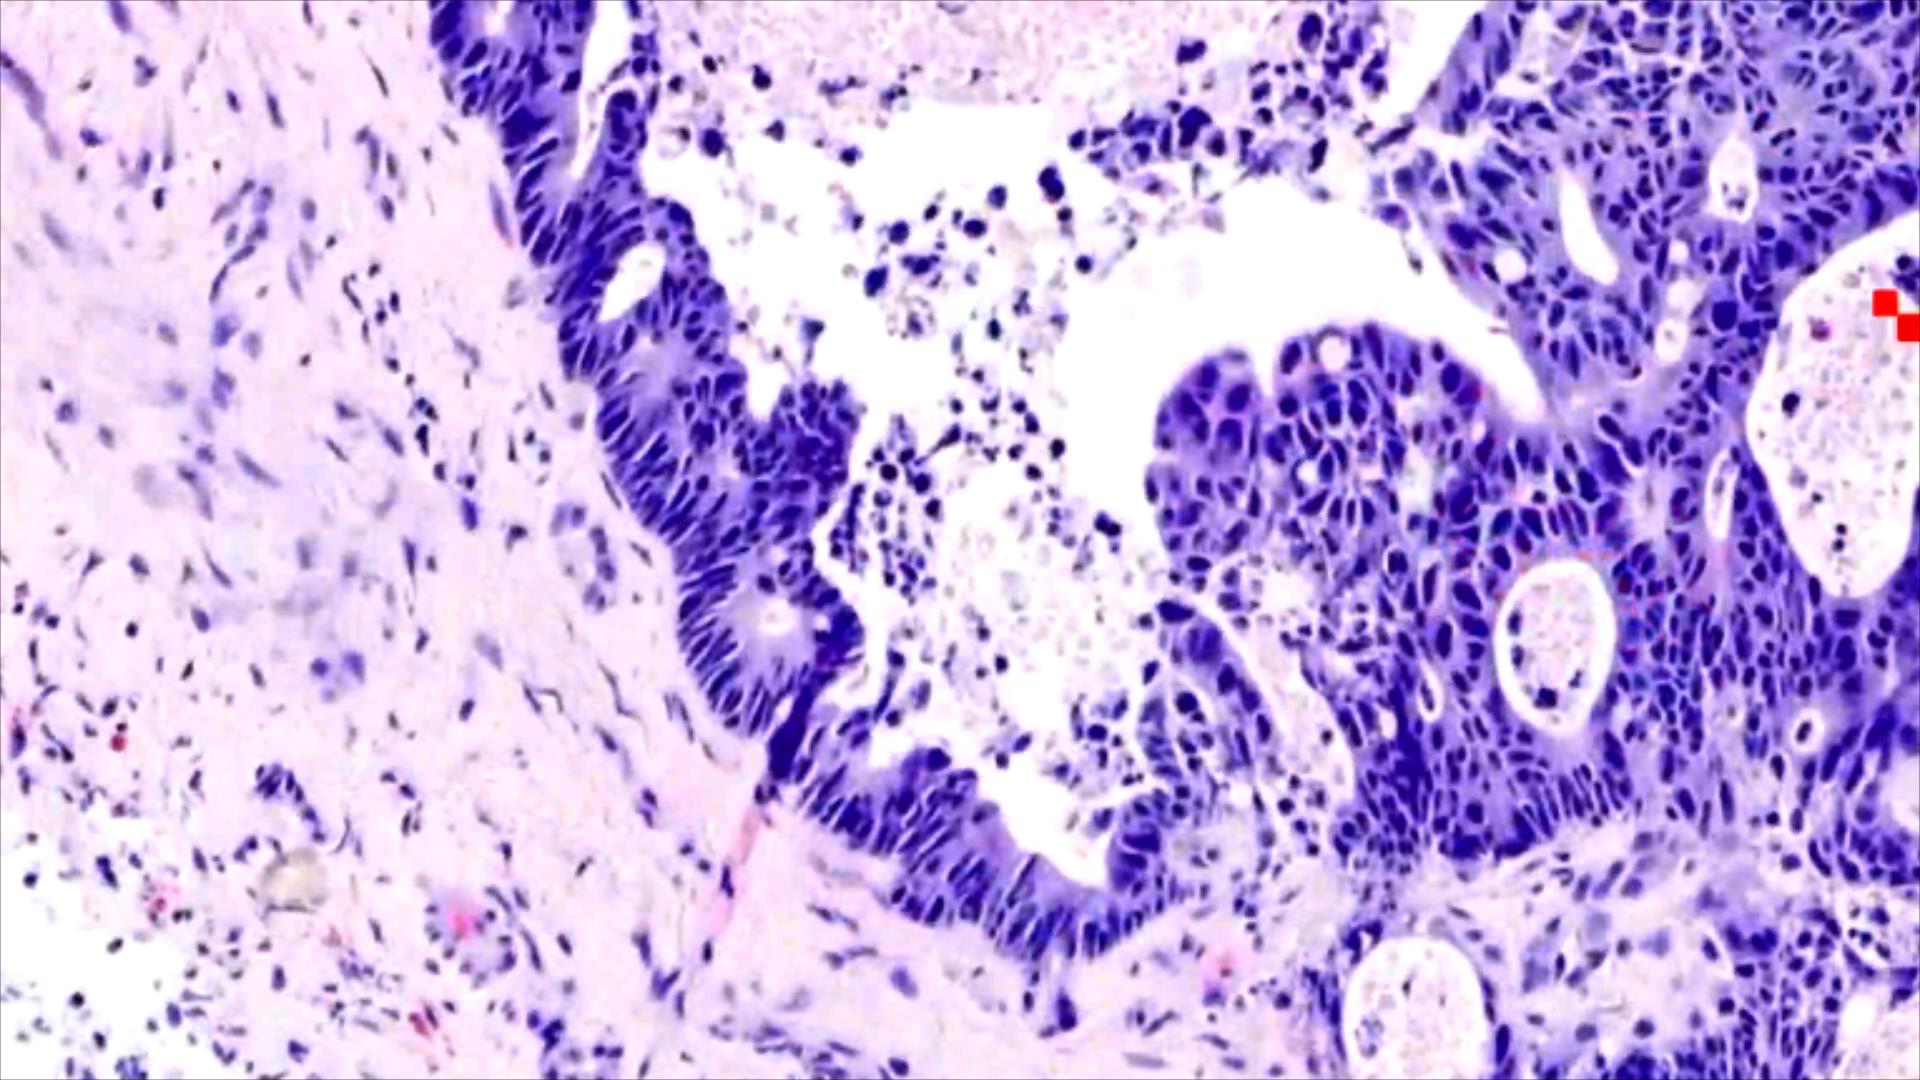

小土豆跟着农人老师学本领-肝占位穿刺组织  腺样结构肿瘤  细胞异型性 腺癌,考虑转移性